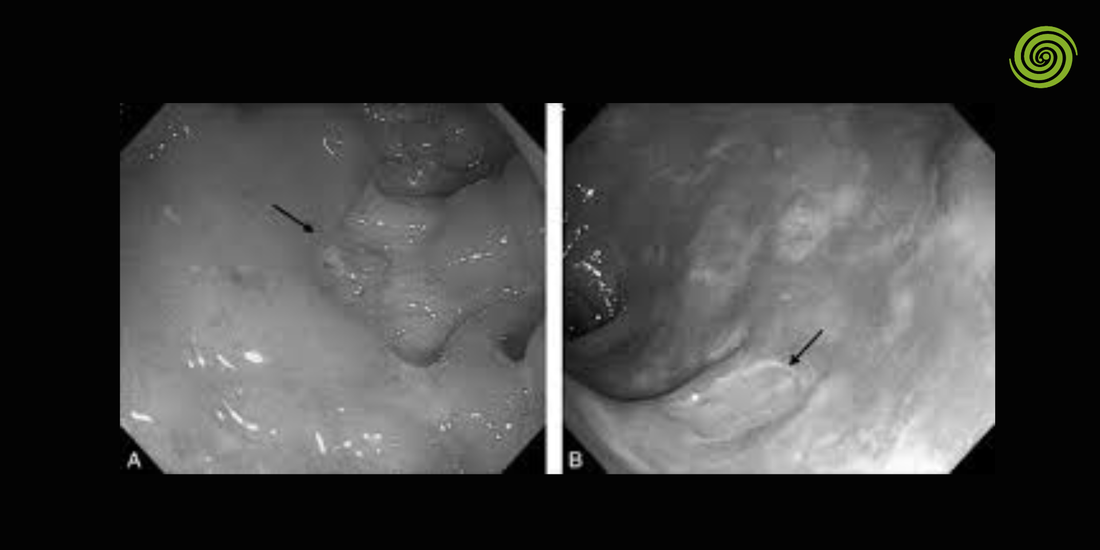

Este procedimiento permite observar el recto y el colon sigmoide mediante un endoscopio flexible equipado con cámara e iluminación. Gracias a esta tecnología, los médicos pueden identificar inflamaciones, pólipos, sangrados o lesiones en esta región del colon.

Las imágenes captadas por la cámara se transmiten en tiempo real a un monitor médico, lo que permite al especialista observar la mucosa intestinal con gran detalle.

Las imágenes transmitidas por la cámara permiten al especialista examinar las paredes del colon.

En algunos casos se pueden realizar biopsias o retirar pólipos durante el procedimiento.